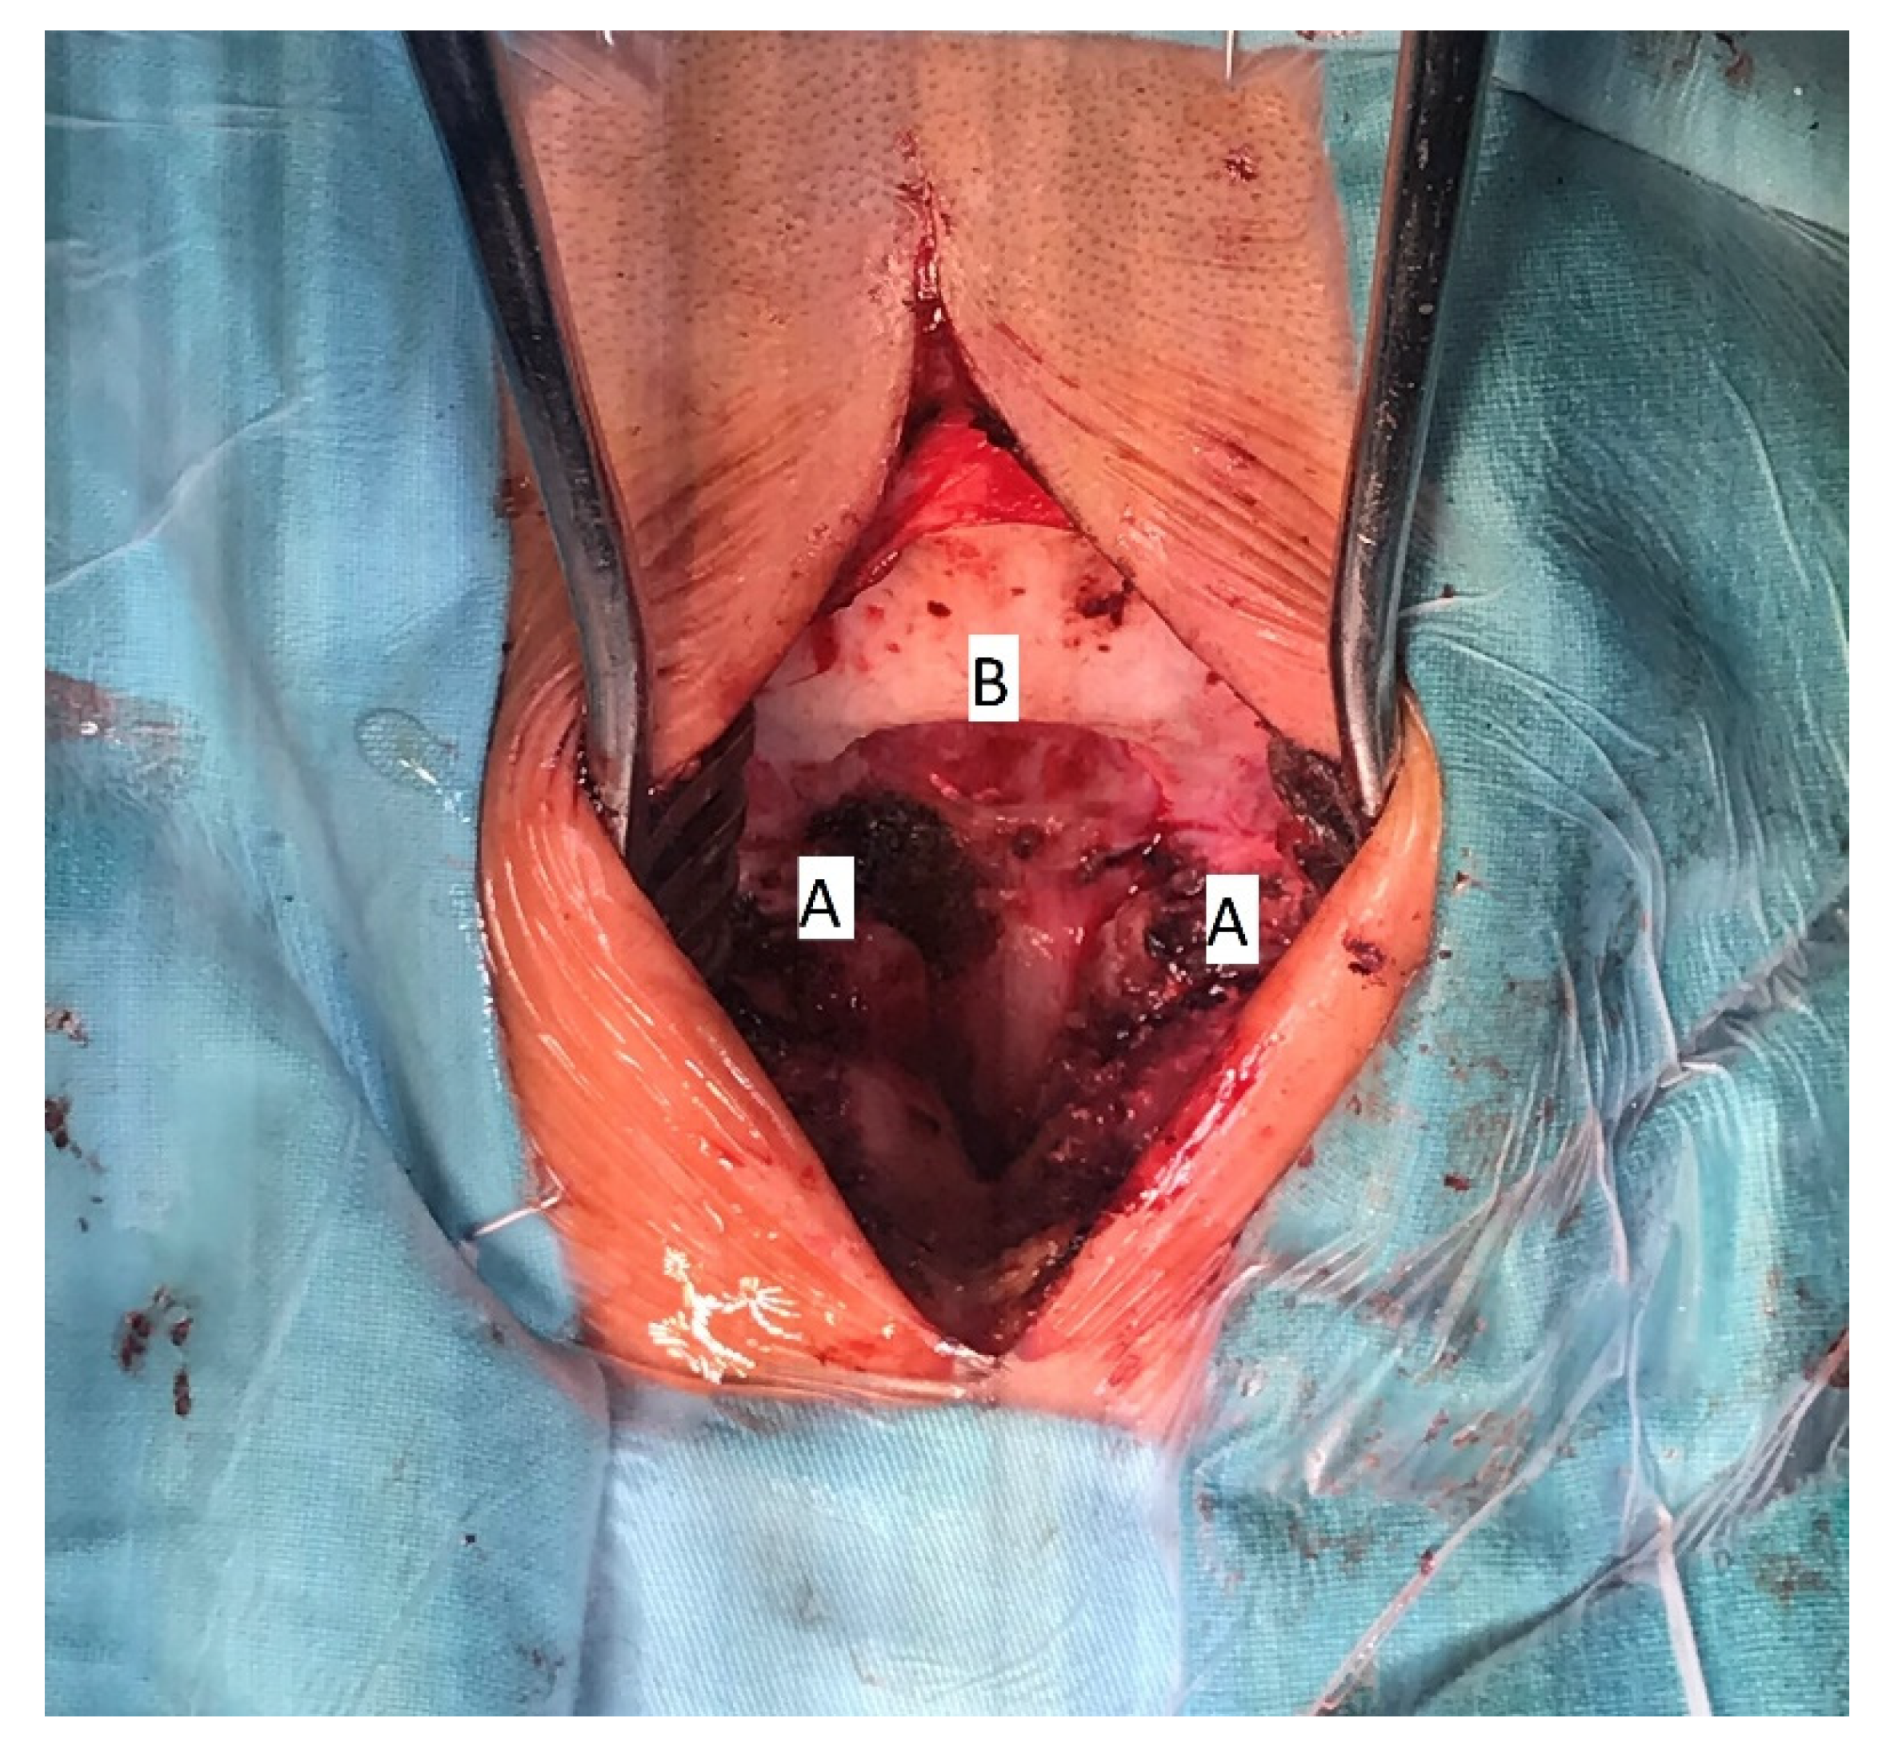

The patient underwent surgical treatment under general anesthesia and in a prone position. The surgical approach was performed in the mediosagittal plane. The foramen magnum was decompressed with a micro-technique using a high-speed drill and a rongeur (Figure 4). The bony part of the bifid lamina and occipital bone were extremely soft. The bifid arch of the C1 vertebra was covered with the fibrous band which was cut as a part of posterior decompression. An adequate decompression of CCJ and regular closure of the wound was obtained.

Figure 4. Intraoperative image of decompressive craniotomy (B); bifid arch of the atlas (A), 15 years of age.